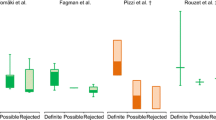

The patients were separated in two groups according to the diagnosis confirmation of IE. Table 1 shows the mean and standard deviation of the uptake metrics in the main valvular regions for the different groups. An overall increase in the myocardial metabolic uptake is observed in the confirmed IE group (Table 1). As shown in Fig. 8, increased values of VHI and RCR can be also noticed within the confirmed IE diagnosis group. Mann–Whitney U test is performed to verify these patterns (Table 1). Despite the observed increased uptake heterogeneity (higher VHI and RCR) tendency for the confirmed IE studies, statistically significant differences are only observed between groups for RCR.

Differences in valve heterogeneity ratios (VHI, RCR) between groups were studied with the receiver operating characteristic (ROC) analysis. Figure 8 shows the ROC curves for VHI and RCR. Both indices present an AUC above 0.7 (AUCVHI = 0.727; AUCRCR = 0.808).

The quantitative metrics showed an increased myocardial metabolic uptake along the different valve regions in the confirmed IE group, which is in the line with the findings of other studies [9, 21]. Additionally, the proposed heterogeneity metrics VHI and RCR showed higher values for the positive IE group, indicating the presence of a high-uptake focus. It should be mentioned that three outliers out of twenty case studies are observed, which is not negligible. However, this could be explained by the limited size and retrospective nature of the study cohort. Nevertheless, the two case outliers with respect to the Confirmed IE group demonstrate that higher RCR values are related to IE confirmation, as expected. The case outlier with respect to the No IE group showed myocardial uptake in the left ventricle, masking valve activity and increasing the ratios. While statistically significant differences could be only observed between groups for RCR, ROC analyses revealed AUCs above 0.7 for both heterogeneity ratios (AUCRCR = 0.808; AUCVHI = 0.727). Further analyses were performed to include the descending aorta blood pool ratio described in the literature [2, 11, 22, 27]. However, the results seem to not improve the diagnostic accuracy of the RCR for our study population (see Supplementary Material). It should be stated that VHI and RCR are aimed at identifying heterogeneous uptake patterns throughout the valvular annulus, that could add value to the quantitative assessment of the infectious process. Tanis et al. [2] found that SUVmax was significantly higher in patients with definite PVIE in comparison with possible or rejected PVIE. However, the prosthetic valve-to-background SUVmax ratio (SUV ratio = SUVmax/SUVmax atrial blood-pool) did not show statistically significant differences between groups. Granados et al. [11] studied the diagnostic accuracy of [18F]FDG PET/CT in patients with suspected IE and Implantable Cardiac Electronic Device (ICED) infection. SUVmax and SUV ratios (SUV ratio 1 = SUVmax/blood-pool SUVmean; SUV ratio 2 = SUVmax/liver SUVmean) demonstrated an overall sensitivity of 91% and specificity of 94%. Pizzi et al. [22] evaluated the SUVmax and prosthetic material-to-background SUV ratio (SUV ratio = SUVmax/SUVmean aortic blood) through ROC curves. A sensitivity of 91% and specificity of 79% were obtained for the SUVmax metric, while the SUV ratio demonstrated an overall sensitivity of 91% and specificity of 76%, with an AUC of 0.89. Swart et. al [27] obtained the ROCs for SUVmax and SUV ratio (SUV ratio = SUVmax/SUVmean aortic blood) in scans of patients suspected of PVE. As a semiquantitative measure of FDG uptake, SUV ratio of ≥ 2.1 was a 75% sensitive and 86% specific predictor of PVE, showing an AUC of 0.83. All the above indicates that the parameters studied might be useful to increase the diagnostic sensitivity of PVIE. In future works, additional quantitative features will be extracted, with special emphasis on radiomic features to obtain potential risk predictors of PVIE.